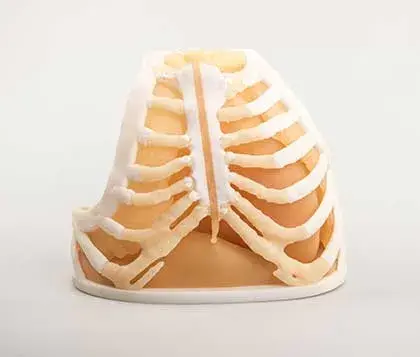

Models printed in flexible, rigid, opaque and clear materials

Translucent and opaque models printed in our high-strength materials*